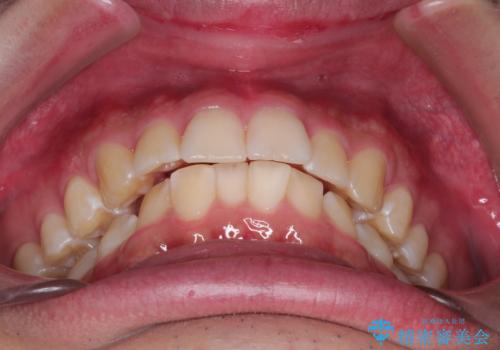

【インビザライン】短期間で出っ歯を治したい

- 出っ歯と口元の突出感が気になるということで来院されました。抜歯矯正も考えられますが、今回は早く終わらせたいという要望があり非抜歯での治療にしました。また遠方から来院されているため、来院回数のおさえられるインビザラインを選択しました。

非抜歯での治療のため、今回はスペース確保のために遠心移動とおもにIPRの処置を取り入れました。